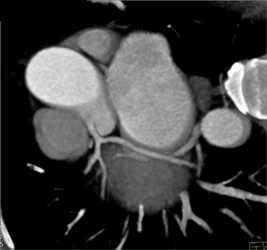

CASE NUMBER 619

Soft and Calcified Plaque